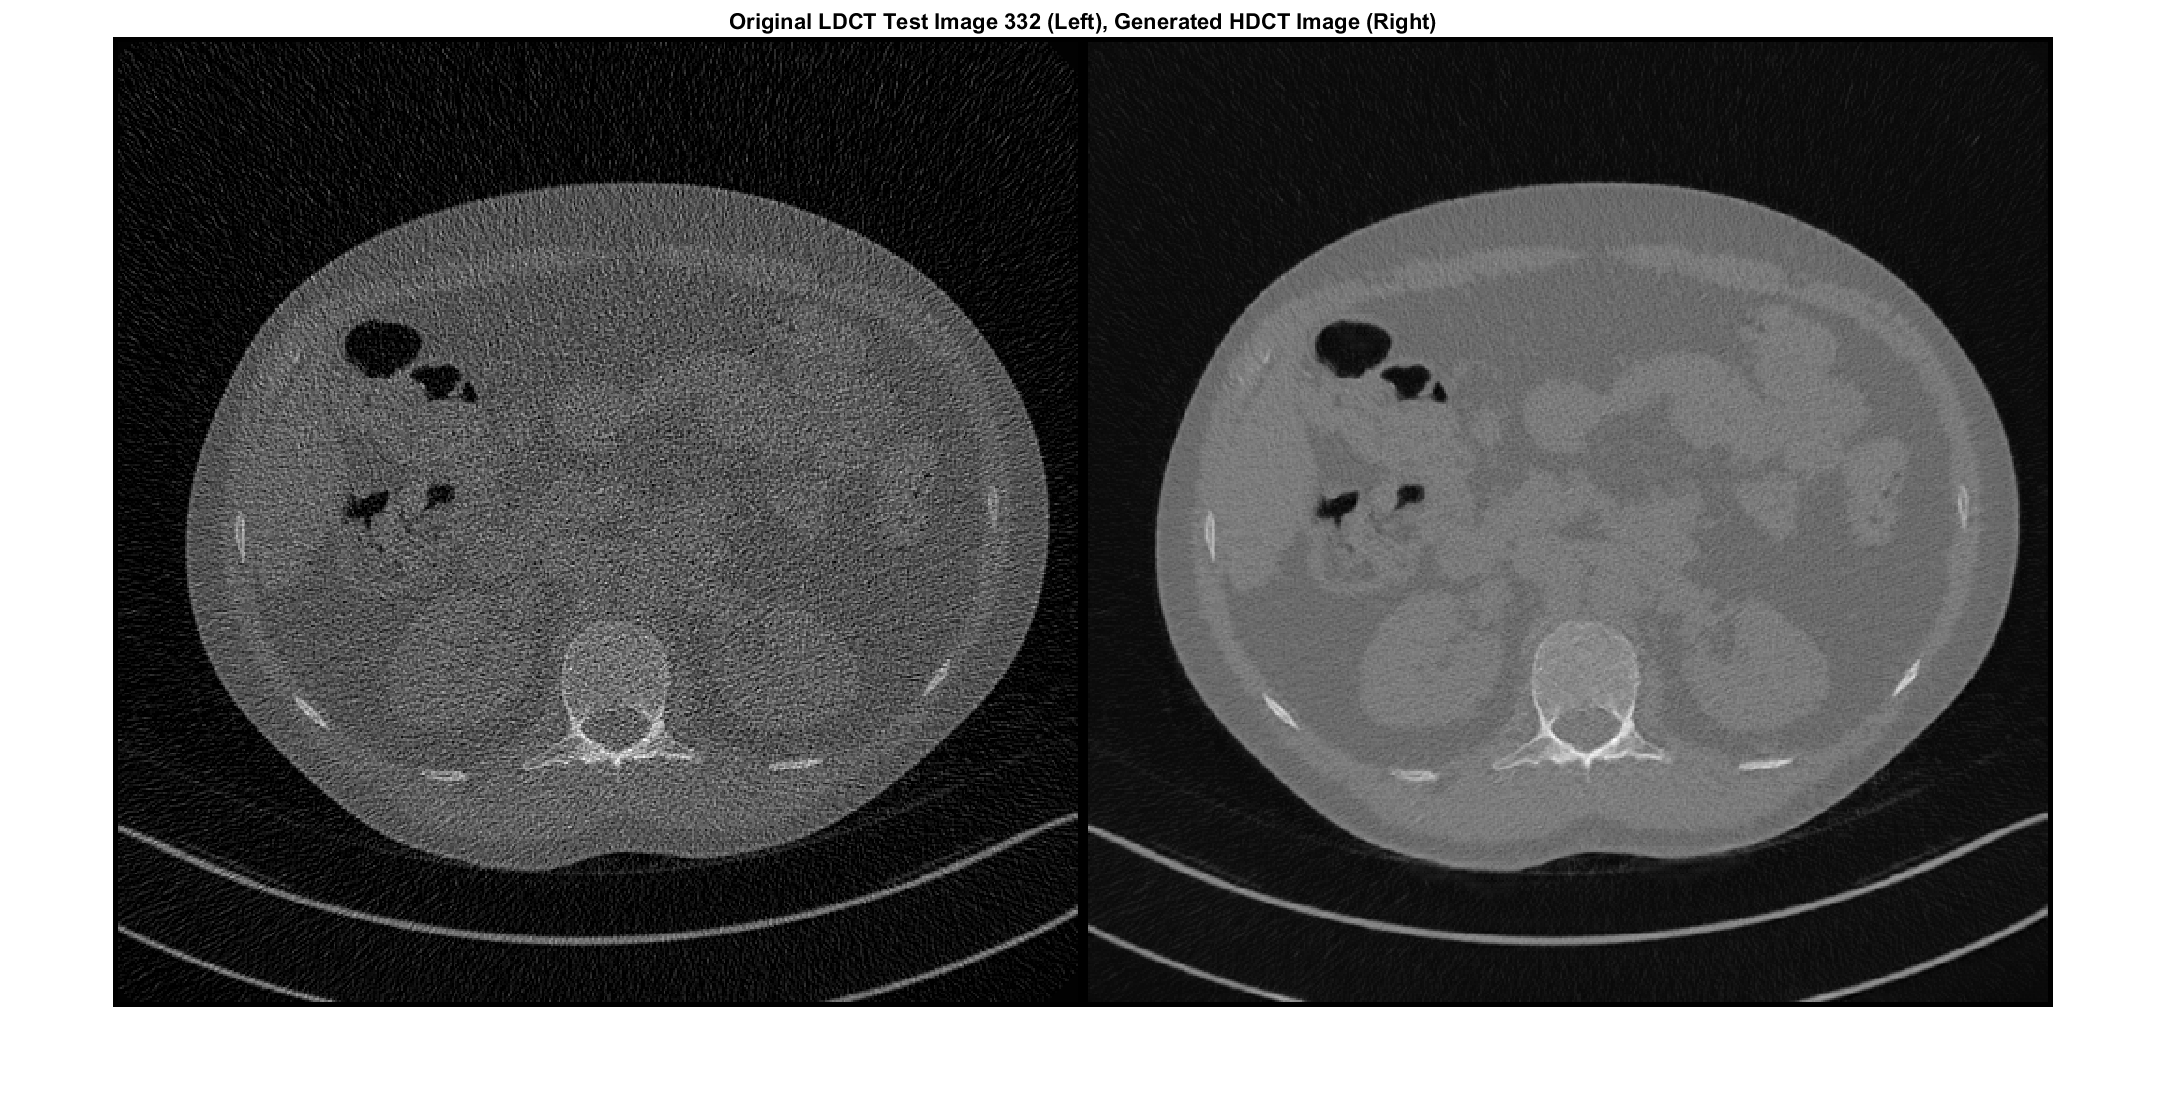

for idx = 1:numTest imageTestLD = read(timdsTestLD); imageTestHD = read(timdsTestHD); imageTestLD = cat(4,imageTestLD{1}); imageTestHD = cat(4,imageTestHD{1}); % Convert mini-batch of data to dlarray and specify the dimension labels % 'SSCB' (spatial, spatial, channel, batch) imageTestLD = dlarray(imageTestLD,'SSCB'); imageTestHD = dlarray(imageTestHD,'SSCB'); % If running on a GPU, then convert data to gpuArray if canUseGPU imageTestLD = gpuArray(imageTestLD); imageTestHD = gpuArray(imageTestHD); end % Generate translated images generatedImageHD = predict(generatorLowDoseToHighDose,imageTestLD); generatedImageLD = predict(generatorHighDoseToLowDose,imageTestHD); % Display a few images to visualize the network responses if ismember(idx,idxImagesToDisplay) figure origImLD = rescale(extractdata(imageTestLD)); genImHD = rescale(extractdata(generatedImageHD)); montage({origImLD,genImHD},Size=[1 2],BorderSize=5) title("Original LDCT Test Image "+idx+" (Left), Generated HDCT Image (Right)") end origPSNR(idx) = psnr(imageTestLD,imageTestHD); generatedPSNR(idx) = psnr(generatedImageHD,imageTestHD); origSSIM(idx) = multissim(imageTestLD,imageTestHD); generatedSSIM(idx) = multissim(generatedImageHD,imageTestHD); end

Вычислите средний PSNR исходных и сгенерированных изображений. Большее значение PSNR указывает на лучшее качество изображения.

disp("Average PSNR of original images: "+mean(origPSNR,"all"));

Average PSNR of original images: 20.4045

disp("Average PSNR of generated images: "+mean(generatedPSNR,"all"));

Average PSNR of generated images: 27.9155

Вычислите средний SSIM исходных и сгенерированных изображений. Значение SSIM ближе к 1 указывает на лучшее качество изображения.

disp("Average SSIM of original images: "+mean(origSSIM,"all"));

Average SSIM of original images: 0.76651

disp("Average SSIM of generated images: "+mean(generatedSSIM,"all"));

Average SSIM of generated images: 0.90194